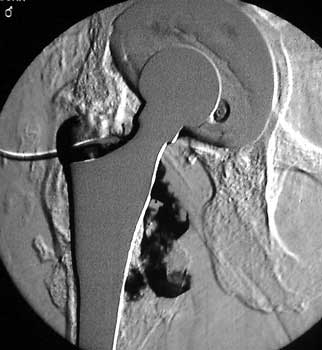

Arthrographic evidence of looseningcontrast enters

abnormally widened interface Gruen zone 1 and 2

Arthrographic evidence of cup looseningcontrast enters

abnormally widened interface Gruen zone II and III